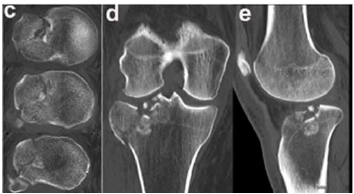

Um paciente de 39 anos de idade, vítima de queda de bicicleta, sofreu trauma no joelho direito. Foi levado ao pronto-socorro do hospital mais próximo, onde foram realizadas as radiografias apresentadas.

O exame de imagem mais apropriado para o estudo do caso é

O exame apresentado indica o envolvimento do platô tibial

Geralmente, o mecanismo de trauma dessas fraturas envolve